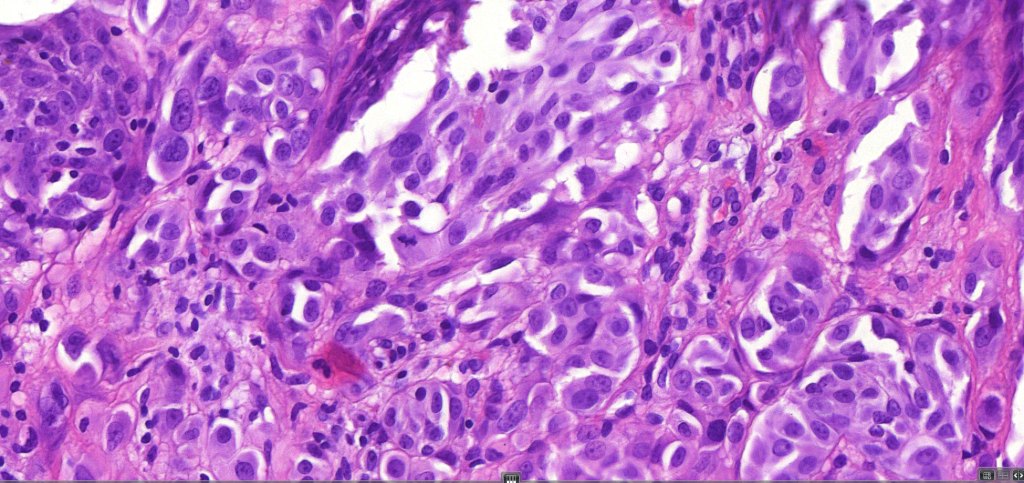

•Epithelioid cell variants often show greater pleomorphism and cells can frequently appear bizarre with abundant, sometimes ground glass cytoplasm and large vesicular nuclei with prominent eosinophilic nucleoli, multinucleate cells are often seen

•Intracytoplasmic pseudoinclusions commonly present in epithelioid cells